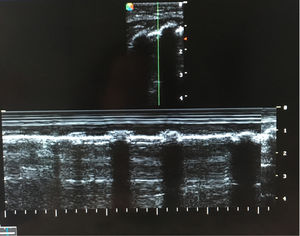

A 4-month-old, ex-premature (24 weeks of pregnancy) patient with severe bronchopulmonary dysplasia on mechanical ventilation (pressure control mode with PIP 25cmH2O, PEEP 5.5cmH2O, respiratory frequency 35rpm and FiO2 30%). On the reported day, the patient required FiO2 of up to 50%, and the chest X-rays (Fig. 1) showed intense hyperinsufflation of the right hemithorax and the absence of the lung sliding sign at pulmonary ultrasound (Fig. 2). In view of the evolution of patients with bronchopulmonary dysplasia towards dynamic compression of the distal airway, we decided to progressively increase PEEP, without ultrasound improvement until PEEP 10cmH2O was reached; at this point pleural sliding was seen to reappear (Fig. 3) and the chest X-rays showed partial resolution of the overdistension (Fig. 4).